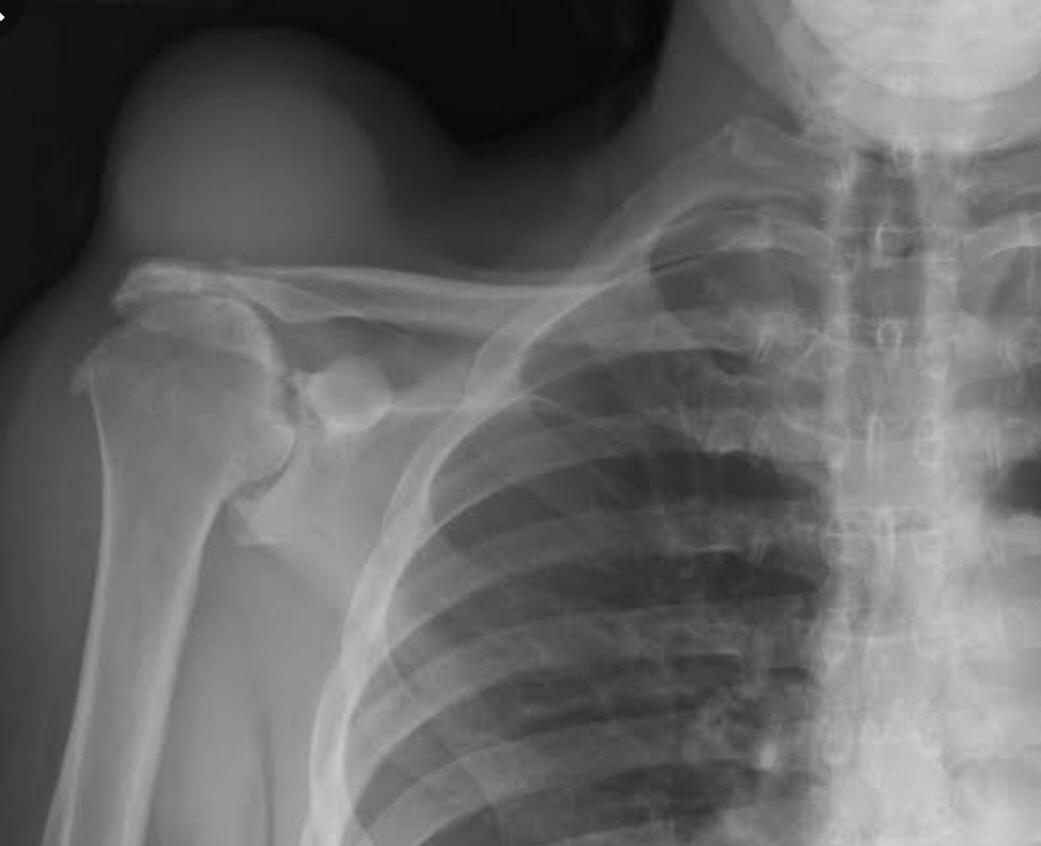

THE GEYSER SIGN IS A SUBCUTANEOUS PSEUDOTUMOR ABOVE THE ACROMIOCLAVICULAR JOINT

The geyser sign is a subcutaneous pseudotumor above the acromioclavicular joint, also known as AC joint cyst. The geyser sign is an infrequently encountered imaging sign that was originally described on conventional fluoroscopy-guided shoulder arthrography. The first case report of these cysts occuring in association with rotator cuff tears was made by Dr. Edward Craig in 1984, and again in 1986. The sign derives its name from its geyser-like appearance.

On physical examination, an AC joint cyst is a palpable fluid-filled mass. MRI scanning or a shoulder arthrogram should be obtained to evaluate the shoulder. Unenhanced MRI scans showing a large rotator cuff tear, a degenerated AC joint, and a large subcutaneous cyst adjacent to the AC joint is virtually patognomonic for the disease. Contrast administration on MR arthrogram will show the synovial fluid or intra-articular contrast extravasates from the glenohumeral joint into the subacromial bursa, into the AC joint, and then into an overlying cystic mass when a full-thickness rotator cuff tear is present, resembling a geyser spouting upwards.

Initial treatment is conservative and involves physical therapy along with aspiration. In patients with functional impairment or chronic shoulder pain who have failed conservative management, surgical treatment is recommended for both excision of the cyst and repair of the rotator cuff tear.